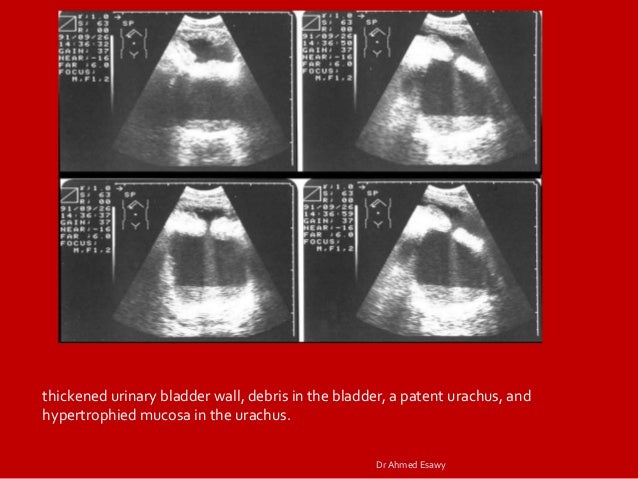

Imaging Cystitis Dr Ahmed Esawy